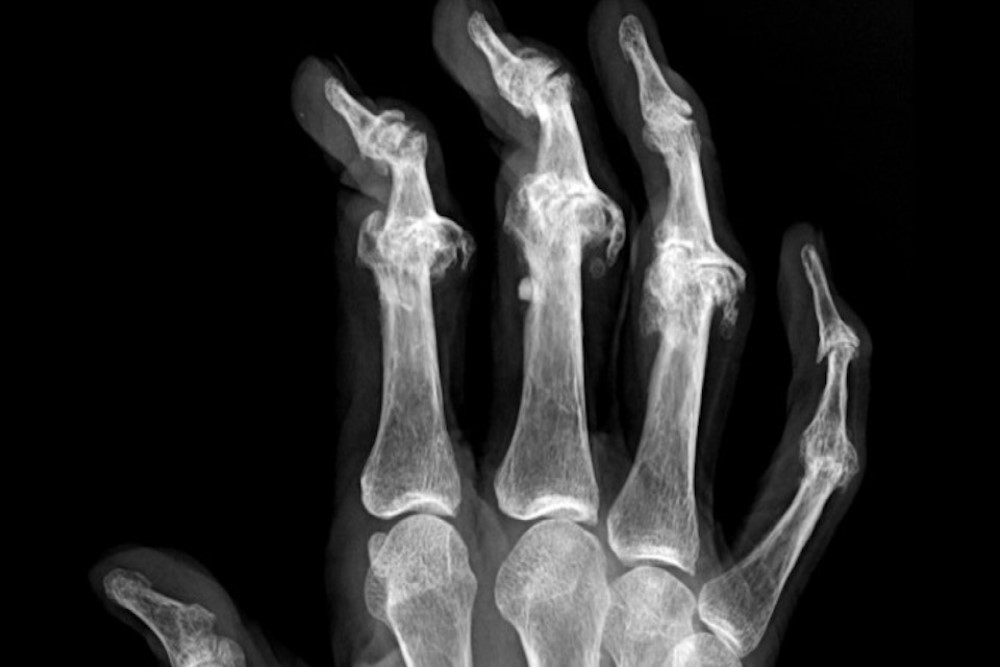

Rheumatologists use a variety of tools to diagnose rheumatic diseases, including a detailed medical history, physical examination, laboratory tests and imaging studies such as X-rays, ultrasound, MRI, or CT scans. They may also perform joint aspirations or biopsies in some cases.